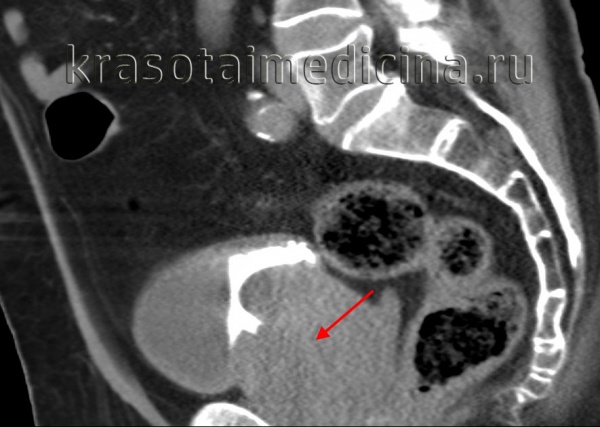

По результатам УЗИ простаты с определением остаточной мочи у пациента выявили признаки узловой гиперплазии, диффузные изменения, калькулёзный простатит и кисту простаты.

- объём предстательной железы — 118 куб. см;

- объём остаточной мочи — 80 мл;

- общий ПСА — 8,54 нг/мл.

- максимальная скорость (Qmax) — 9 мл/сек.;

- средняя скорость — 6 мл/сек.